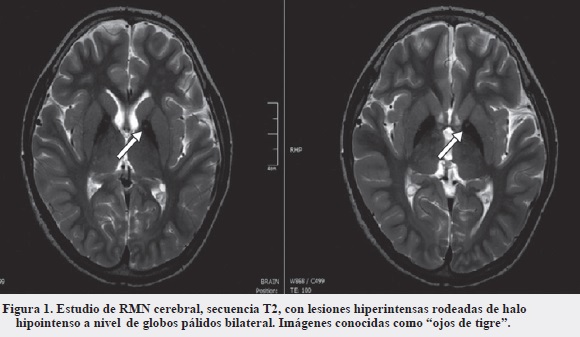

Al examen se evidenciaron movimientos distónicos generalizados e hiperreflexia musculotendinosa, trastorno del habla y déficit cognitivo. Se iniciaron estudios. Los ácidos orgánicos urinarios cualitativos, el perfil de acilcarnitinas y la relación ácido láctico/piruvato fueron normales; el estudio para Nieman Pick tipo C también fue negativo, la resonancia magnética cerebral inicial normal y el estudio molecular para atrofia espinocerebelosa fue negativo. El paciente presenta progresión de las distonías, con presencia de tormenta distónica en dos ocasiones. Se realizó manejo con múltiples fármacos, incluida bomba de baclofeno, sin mejoría. Se realiza resonancia magnética cerebral de tres teslas con cortes finos de ganglios basales, informándose hiperintensidad de globos pálidos bilateral, con halo de hipointensidad, imagen conocida como "ojos de tigre" que sugiere depósito de hierro (Figura 1).

Los casos típicos como atípicos y fenotipo HARP pueden presentar en la fase presintomática el signo de "ojos de tigre". En la secuencia ponderada en T2 se evidencia hiperintensidad en el globo pálido por la vacuolización y gliosis del tejido, rodeado de halo hipointenso por depósito de hierro hallado en las autopsias, con alta correlación con la mutación PANK2. Este hallazgo puede estar ausente en estadios tempranos de la enfermedad (1, 7, 19).

La hiperintensidad palidal central puede desvanecerse a medida que progresa la enfermedad; la identificación de este signo debería impulsar un alto índice de sospecha de PKAN. Los casos de otras neuroferritinopatías con presuntos "ojos de tigre" suelen ser atípicos en apariencia, una cuidadosa evaluación revela contorno irregular y/o desplazamiento lateral de la hiperintensidad central (1, 6, 20).